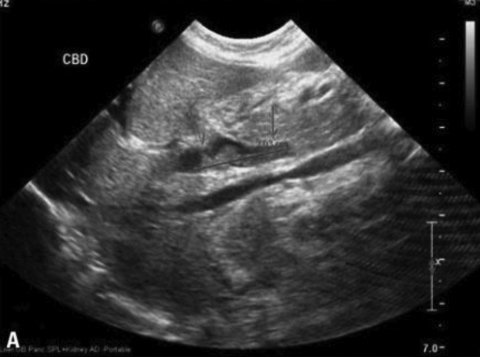

Для подтверждения синдрома сгущения желчи или выявления его ранних признаков используются инструментальные методы, в первую очередь УЗИ. Основными признаками синдрома сгущения желчи являются умеренная дилатация интрапеченочных отделов билиарного тракта, увеличение диаметра общего желчного протока (иногда до 12,3 мм), густая вязкая желчь (осадок низкой эхогенности) в желчном пузыре и желчных протоках (рис. 1) [3, 5].

Рисунок 1. Синдром сгущения желчи. Дилатация общего желчного протока. Билиарный сладж в общем желчном протоке [21]

Figure 1. Bile thickening syndrome. Dilatation of the common bile duct. Biliary sludge in the common bile duct [21]

Диаметр общего желчного протока у детей первых 3 мес. жизни не должен превышать 1–1,2 мм. Как показали результаты УЗИ, проанализированных E. Fitzpatrick в 2010 г. у 878 детей первых трех месяцев жизни с холестазом, дилатация общего желчного протока более 1,2 мм (от 1,2 до 12,3 мм) была обнаружена в 9% случаев. На долю детей с синдромом сгущения желчи в этой группе приходилось 71,1%. Доказано, что дилатация общего желчного протока более 3 мм характерна для синдрома сгущения желчи (чувствительность 100% и специфичность 87%). Ниже мы приводим ультразвуковые признаки изменения желчи, полностью подтверждающие дословный перевод термина “Inspissated bile syndrome” – синдром «грязной желчи» (исследование проведено врачом отделения лучевой диагностики больницы им. З.А. Башляевой Ю.А. Бронниковой). На фотографиях с монитора (рис. 2А) видно, что содержимое желчного пузыря неоднородно, при внимательном осмотре обращает внимание осадок в области дна. Использование более чувствительного датчика и увеличение изображения на экране монитора (рис. 2B) позволяет более четко рассмотреть наличие осадка в желчном пузыре и подтвердить наличие синдрома сгущения желчи [22, 23].